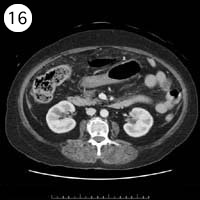

57歳 女性

単純CT

造影CT